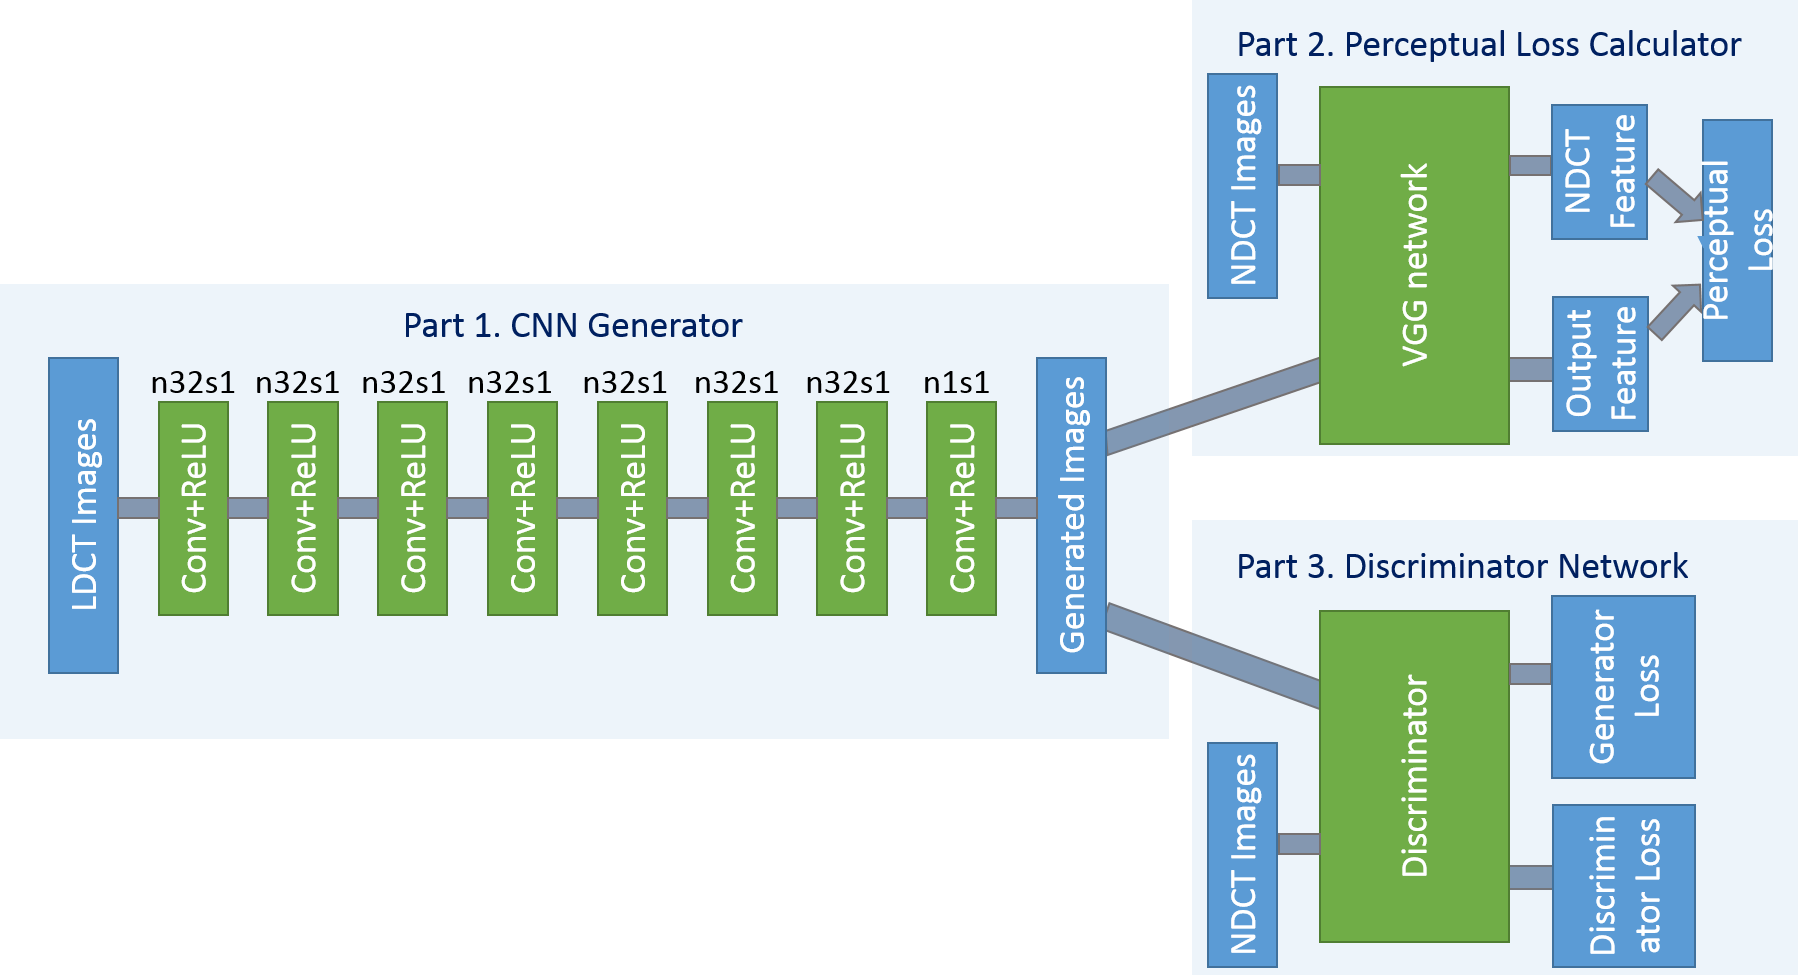

The overall view of the proposed network structure is shown in Fig. 1. For convenience, we name this network WGAN-VGG. It consists three parts. The first part is the generator , which is a convolutional neural network (CNN) of 8 convolutional layers. Following the common practice in the deep learning community [44], small kernels were used in each convolutional layer. Due to the stacking structure, such a network can cover a large enough receptive field efficiently. Each of the first 7 hidden layers of have 32 filters. The last layer generates only one feature map with a single filter, which is also the output of . We use Rectified Linear Unit (ReLU) as the activation function.

The second part of the network is the perceptual loss calculator, which is realized by the pre-trained VGG network [43]. A denoised output image from the generator and the ground truth image are fed into the pre-trained VGG network for feature extraction. Then, the objective loss is computed using the extracted features from a specified layer according to Eq. (6). The reconstruction error is then back-propagated to update the weights of only, while keeping the VGG parameters intact.

The third part of the network is the discriminator . As shown in Fig. 2, has 6 convolutional layers with the structure inspired by others’ work [43, 29, 30]. The first two convolutional layers have 64 filters, then followed by two convolutional layers of 128 filters, and the last two convolutional layers have 256 filters. Following the same logic as in , all the convolutional layers in have a small kernel size. After the six convolutional layers, there are two fully-connected layers, of which the first has 1024 outputs and the other has a single output. Following the practice in [31], there is no sigmoid cross entropy layer at the end of .